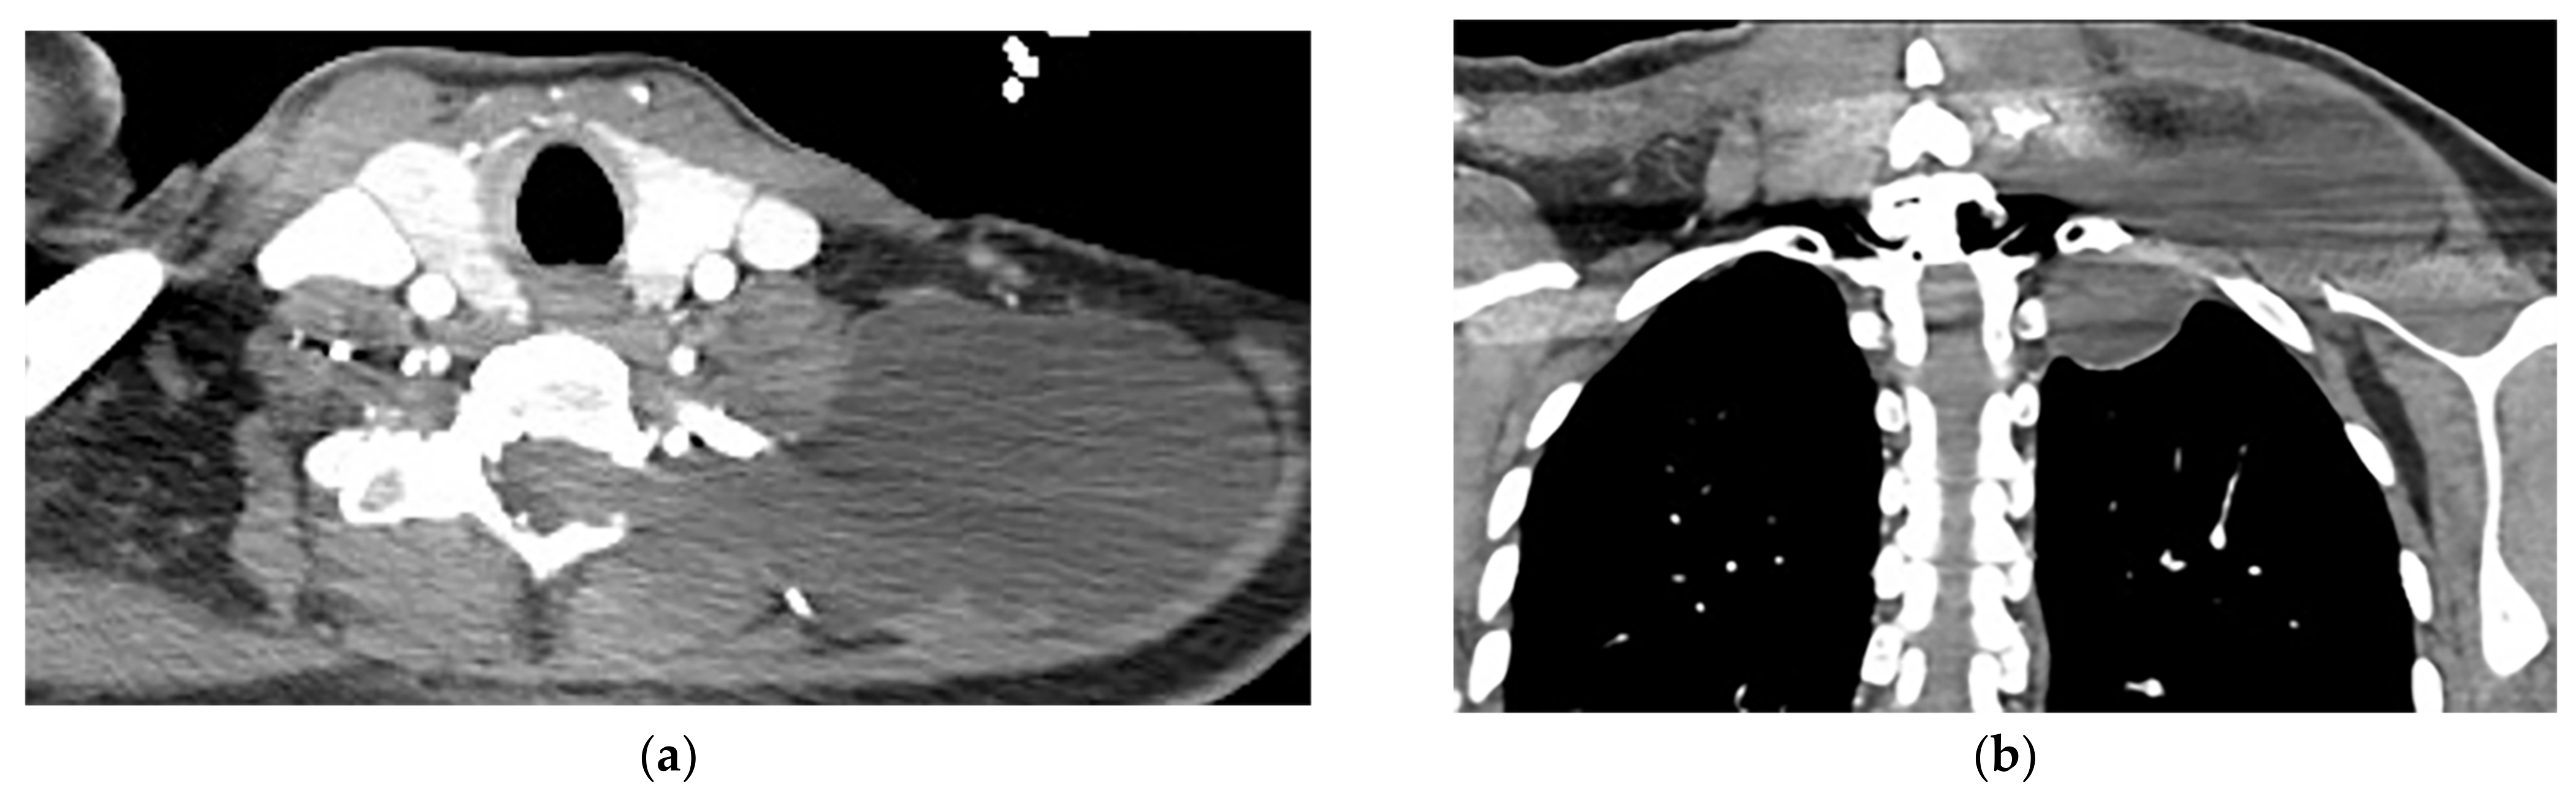

11.1. Empyema Necessitance

| Empyema necessitance | Connection of pleural collection to extrapleural mass, soft tissue inflammation, rib destruction with periosteal reaction, and fluid collection. | T1W: hypointense effusion and fluid collection T2W: hyperintense effusion, increased thickness of extrapleural fat, and chest wall muscles with hyperintense on T2WFS T1WFS + C: pleural and septal enhancement |